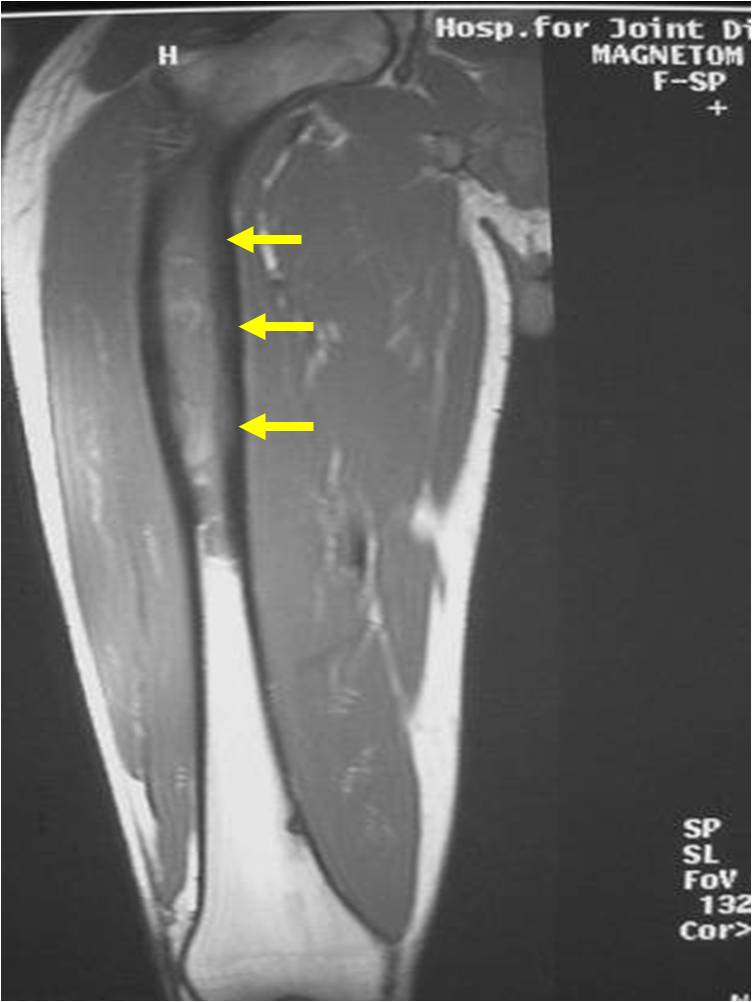

- Soft Tissue Mass in 90% of of cases

- Ewing sarcoma is one of the most aggressive tumors

- High propensity for Local recurrences

- Distant metastases (predominantly in lungs and other bones)

- Ewing sarcoma responds well to chemotherapy. Often there is a dramatic reduction in size of the tumor.

- Lesions grossly confined to bone have a better prognosis than those with a soft tissue component